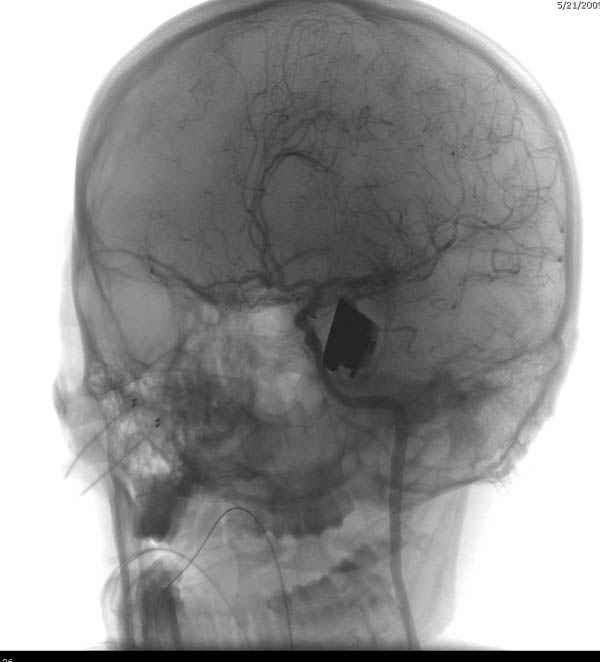

В своих выступлениях я рассказывал, что наши центры в мирное время по пенетрирующим травмам не уступает Ираку или Афганстану, и вот недавно к нам поступила больная 22 лет, травма "ножом в глаз" от бывшей подруги нынешнего "бой френда".

При поступлении в сознании, жаловалась на неприятные ощущения в глазнице.

По протоколу сделаны все необходимые исследования: рентген, ангиограмма с 3Д реконструкцией, где обнаружили что все жизненно важные сосуды не задеты, даже некоторые "сидят" изгибаясь на ноже.